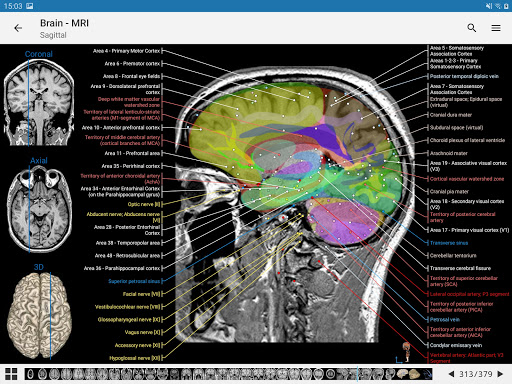

-The pins mode have a new behaviour allowing you to follow an anatomical structure much more easily

-You can now manually select the font size you prefer for your anatomical structures labels (in labels mode)

-Within the details view of an anatomical structure, a pin now points the related structure in all present images

Also tap directly on the image to navigate to the presented image in that module